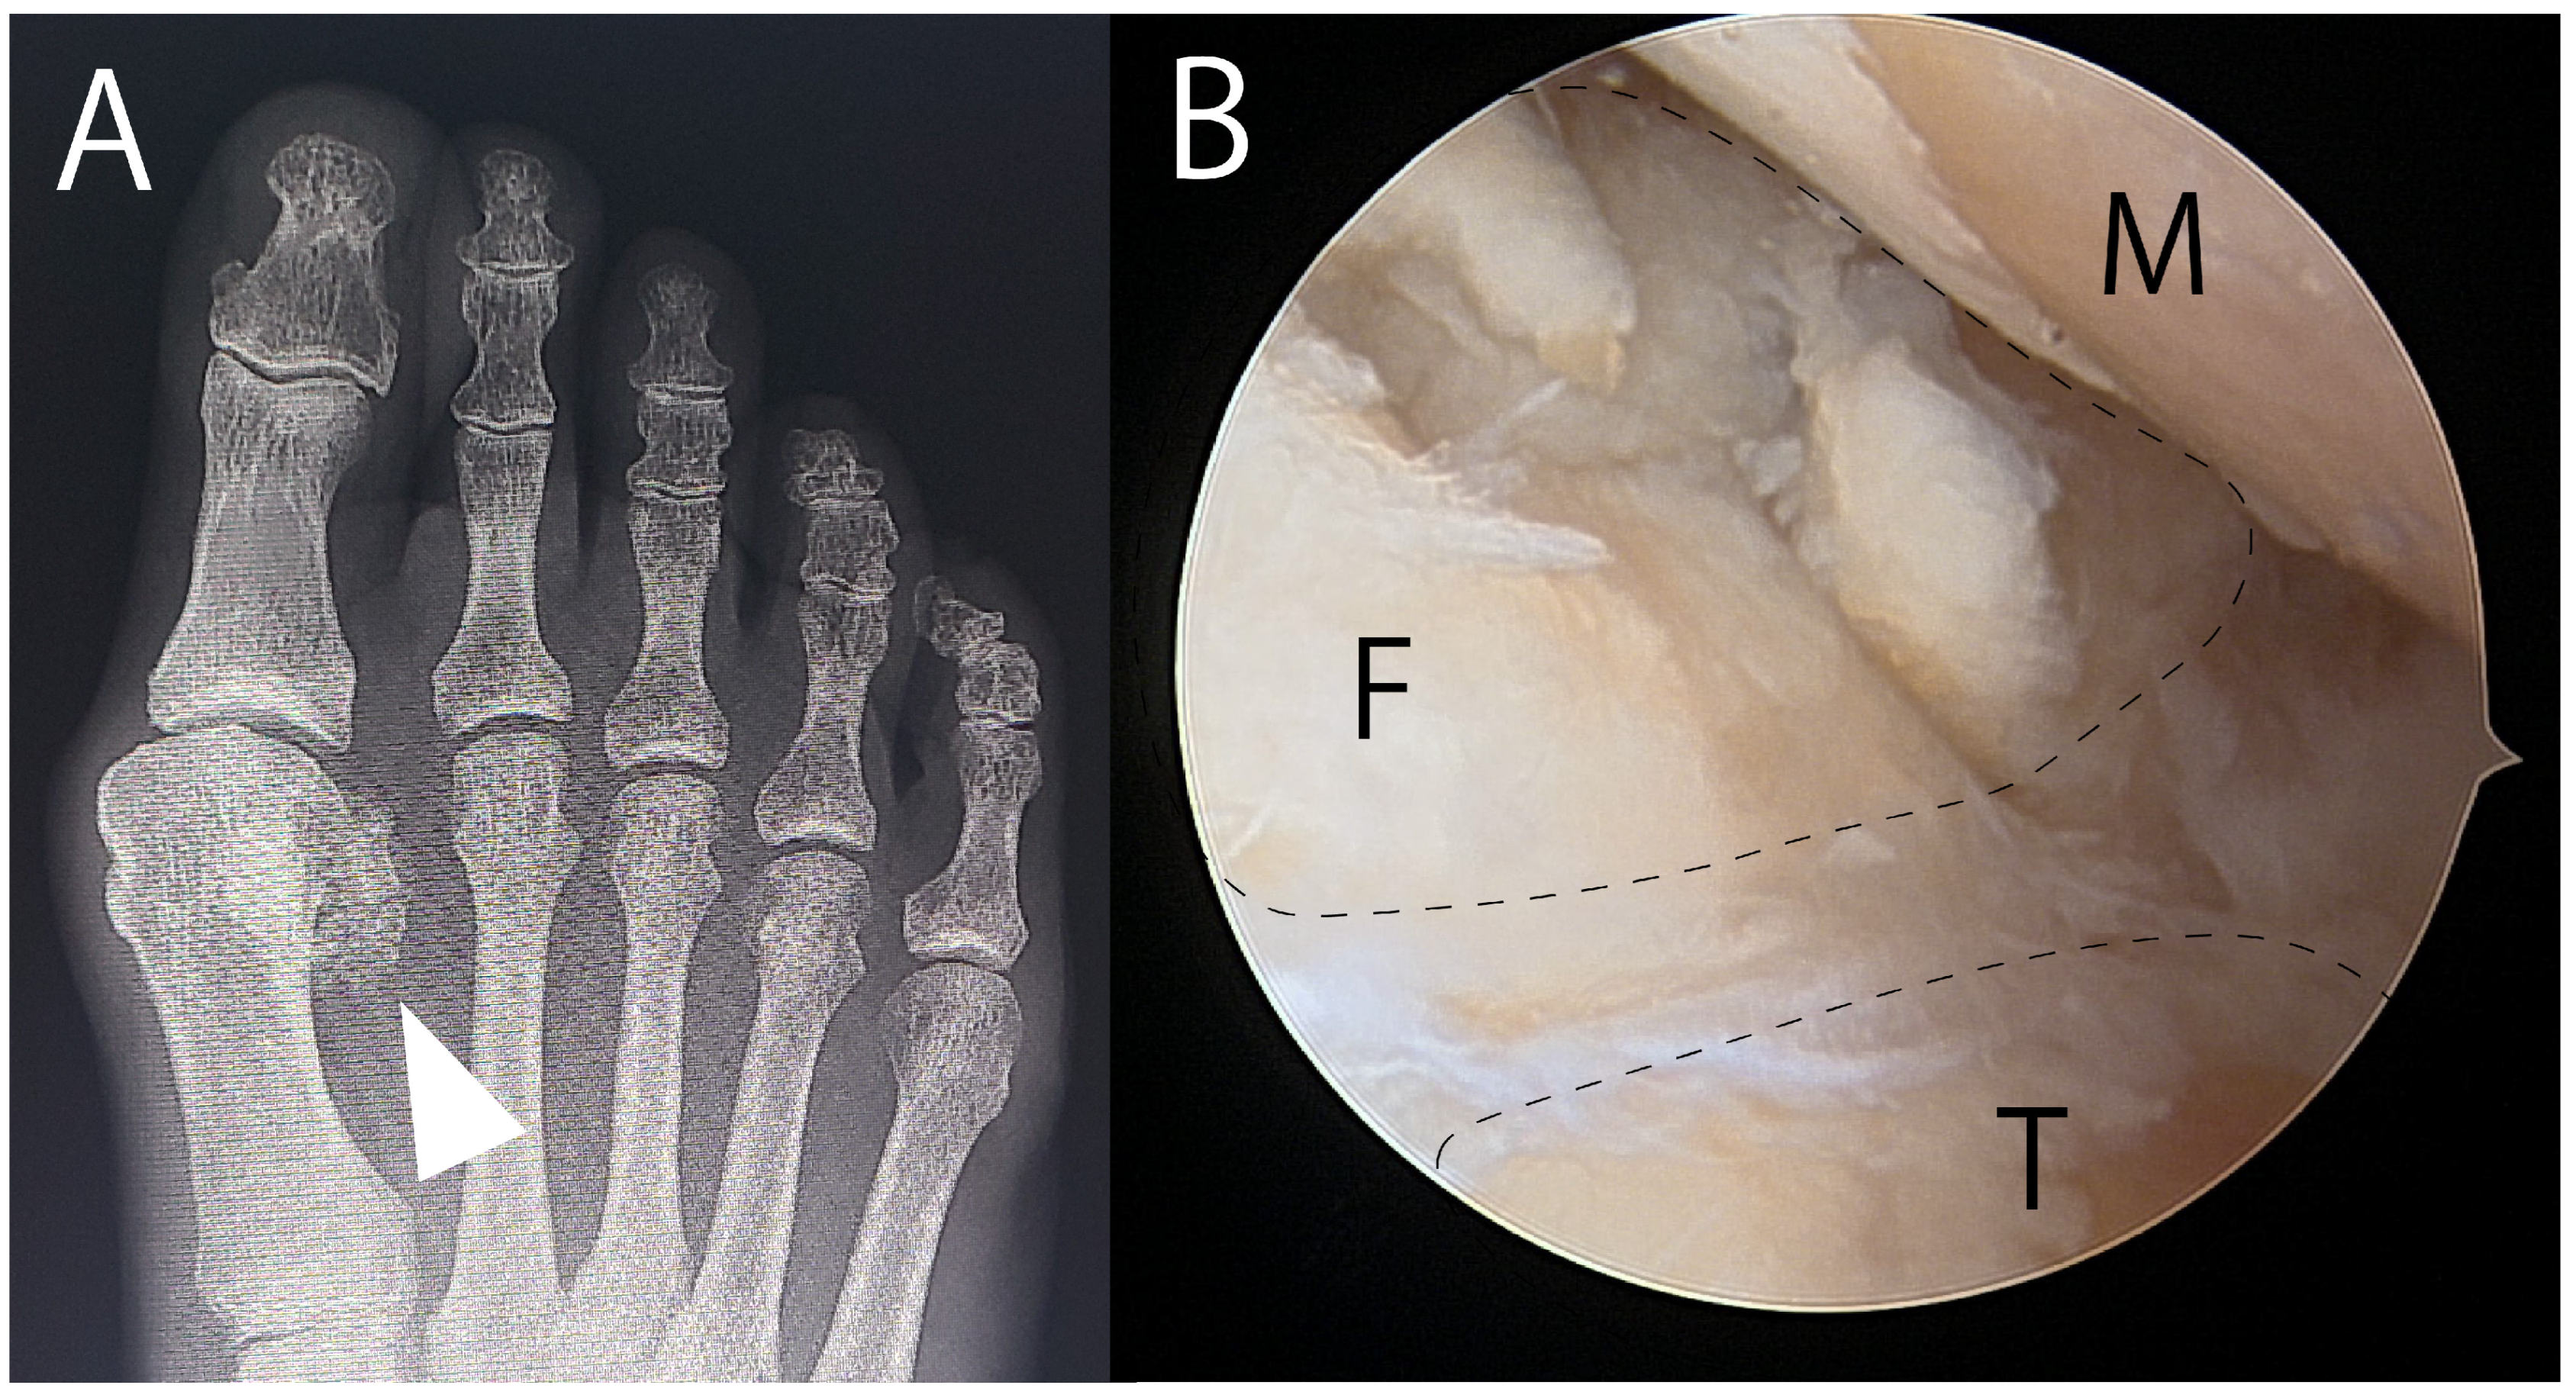

- Nakajima, K. Arthroscopic autologous bone grafting for hallux sesamoid fracture nonunion results in a high rate of complete resolution. Arthrosc. Sports. Med. Rehabil. 1789, 4, e1789–e1797. [Google Scholar] [CrossRef]

| Nakajima (2022) [73] | Case series 11 (10 tibial, 1 fibular) | Arthroscopic bone grafting | VAS 72.0 → 12.0 VAS of 0 and JSSF of 100 observed in 9/11 | Persistent pain (2/11) |